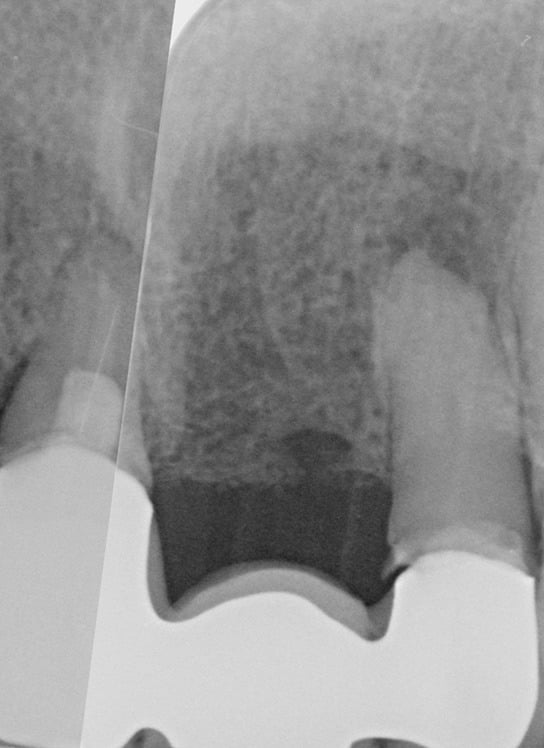

The fixture (titanium screw) replaces the function of a natural tooth root. Your jawbone attaches to the titanium threads of the fixture, providing a completely stable foundation for the new crown – a process known as osseo-integration. It usually takes twelve weeks for the bone to securely bond to the entire fixture surface.

Your natural teeth are stable biting and chewing surfaces because your jawbone supports them. This is also true of dental implants. Successful dental implants become firmly embedded in the jaw through osseointegration, a natural process where the bone grows onto the implant surface.

This provides the same stability as natural teeth, making it possible for your replacement teeth to look, feel and function like natural teeth.